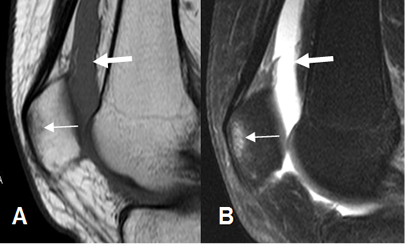

Fig 51. Contusión de la patela.

A: RM sagital en T1 y B: RM sagital en STIR. Trauma directo, con área hipointensa en T1 e hiperintensa en STIR, que corresponde a contusión. Existe hemartrosis asociada. (Flechas gruesas).